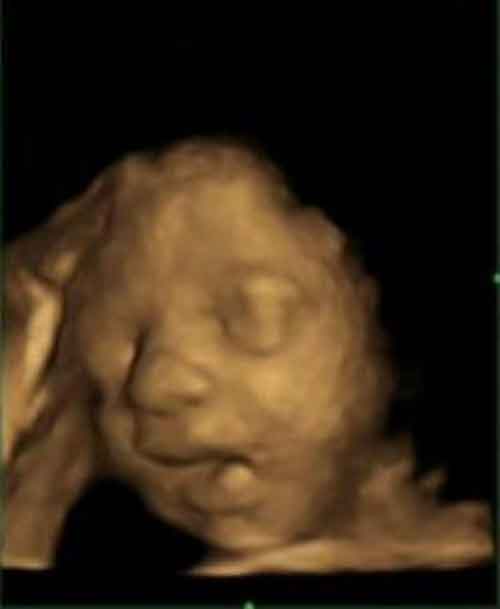

I bimbi sbadigliano già quando sono ancora nel pancione. E’ stato un gruppo di ricercatori britannici, guidati da Nadja Reissland dell’Università di Durham, a distinguere questi sbadigli da altri più semplici movimenti della bocca, scoprendo che alla ventiquattresima settimana di gestazione più della metà dei movimenti delle labbra sono veri e propri sbadigli. A partire dalle 28 settimane di gravidanza il loro numero diminuisce, ma secondo i risultati riportati dalla rivista PLoS One, la frequenza con cui il piccolo sbadiglia nelle fasi precedenti potrebbe essere utilizzata per rilevare il suo corretto sviluppo.

Lo studio ha previsto il monitoraggio di 8 femmine e 7 maschi con un tipo di ecografia di ultima generazione – detta 4D – che visualizza l’immagine tridimensionale del bambino in movimento nel grembo materno in tempo reale. L’analisi è stata condotta a 24, 28, 32 e 36 settimane di gestazione. Gli sbadigli sono stati distinti dagli altri movimenti della bocca in base al tempo necessario per raggiungere l’apertura massima della bocca, che nel caso degli sbadigli corrisponde a più del 50% del tempo totale.

Foto: Reissland N, Francis B, Mason J (2012) Development of Fetal Yawn Compared with Non-Yawn Mouth Openings from 24–36 Weeks Gestation. PLoS ONE 7(11): e50569. doi:10.1371/journal.pone.0050569